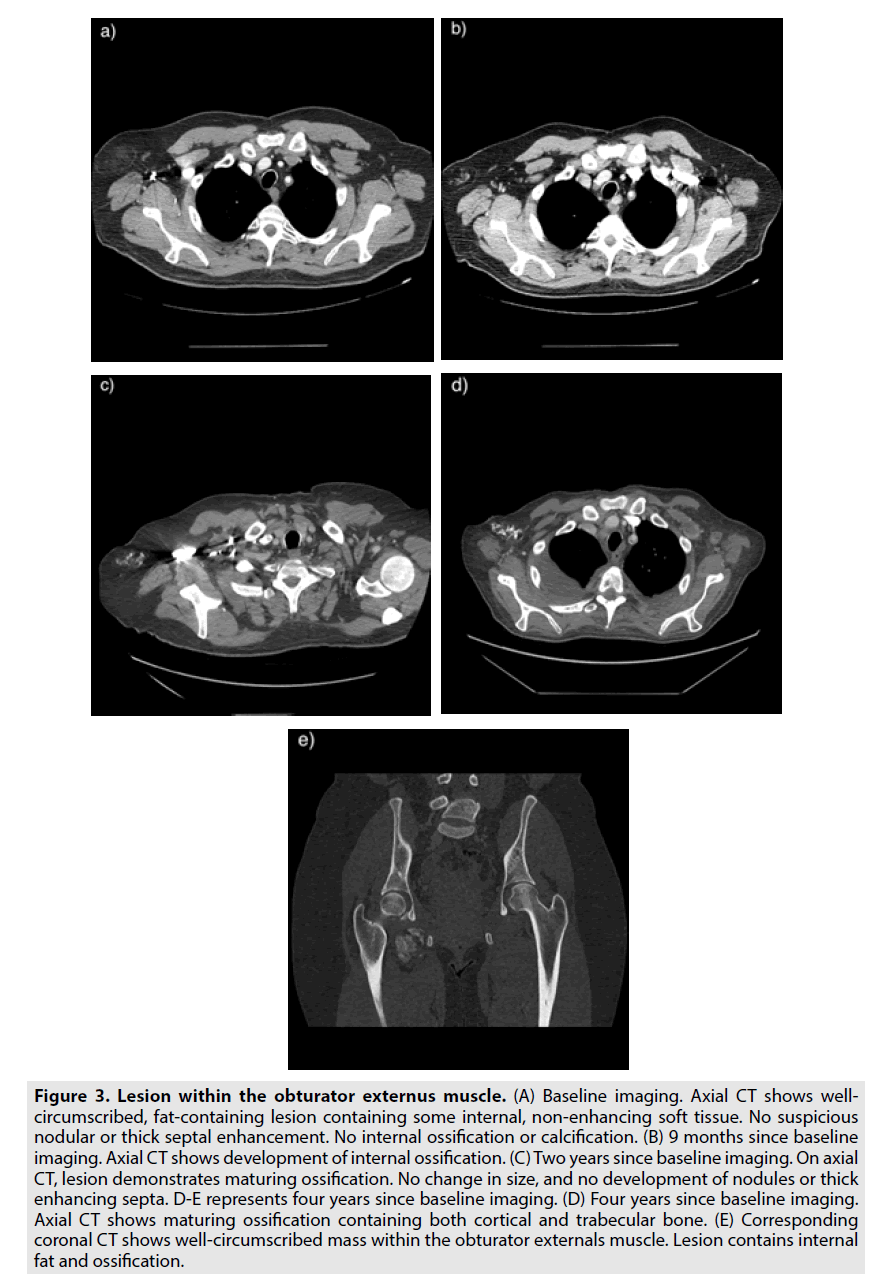

Imaging is important in distinguishing benign ossifying lipoma from more aggressive tumors such as well-differentiated liposarcomas. Ossifying lipomas maintain a stable size and show maturing ossification over time, consistent with a long-standing indolent process (Figures 2 and 3). More aggressive tumors are more likely to contain thickened septa greater than 2 mm and nodular arrangements of non-adipose tissue representing internal de-differentiated elements, whereas ossifying lipoma shows thin internal septa and lacks nodular enhancement. More aggressive tumors are also more likely to have a larger overall size within a subfascial area of the body and consist of a lower composition of fatty tissue by percentage. Furthermore, liposarcomas come to resemble adipose tissue more closely as they become differentiated. In other words, a tumor consisting mostly of fatty tissue with thickened, irregular septa and nodular areas of non-adipose tissue is more likely a liposarcoma than an ossifying lipoma.

Figure 3. Lesion within the obturator externus muscle. (A) Baseline imaging. Axial CT shows wellcircumscribed, fat-containing lesion containing some internal, non-enhancing soft tissue. No suspicious nodular or thick septal enhancement. No internal ossification or calcification. (B) 9 months since baseline imaging. Axial CT shows development of internal ossification. (C) Two years since baseline imaging. On axial CT, lesion demonstrates maturing ossification. No change in size, and no development of nodules or thick enhancing septa. D-E represents four years since baseline imaging. (D) Four years since baseline imaging. Axial CT shows maturing ossification containing both cortical and trabecular bone. (E) Corresponding coronal CT shows well-circumscribed mass within the obturator externals muscle. Lesion contains internal fat and ossification.